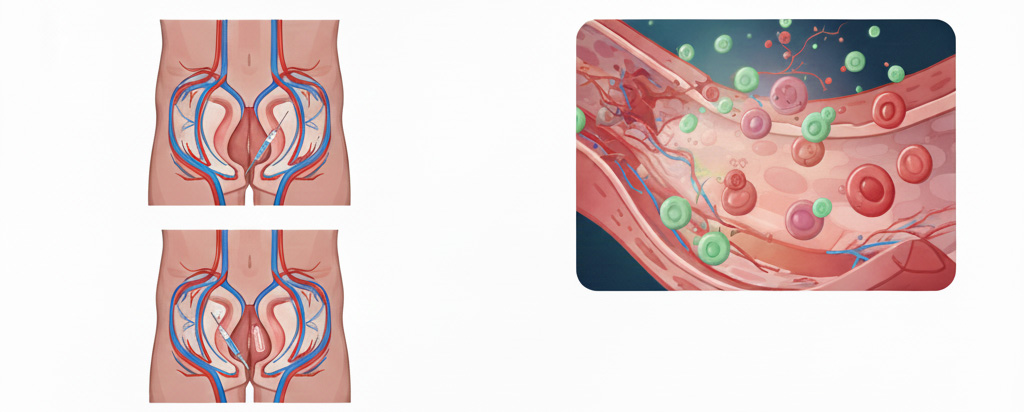

1. 海綿体ボトックス:血管を広げて血流を最大化

ボトックス(ボツリヌス毒素)には、筋肉の緊張を和らげる働きがあります。これを海綿体に注入することで、血管周囲の筋肉がリラックスし、血液が流れ込みやすい状態を強制的に作り出します。

メリット:持続期間が数ヶ月と長く、行為のたびに薬を飲む必要がなくなります。

2. エクソソーム:細胞レベルでの再生・修復

エクソソームは、細胞間の情報伝達を行う物質で、強力な「組織修復能力」を持っています。加齢や生活習慣病で傷ついた血管内皮細胞や神経をケアすることで、EDの原因に根本からアプローチします。

メリット:一時的なしのぎではなく、勃起機能そのもののボトムアップが期待できます。